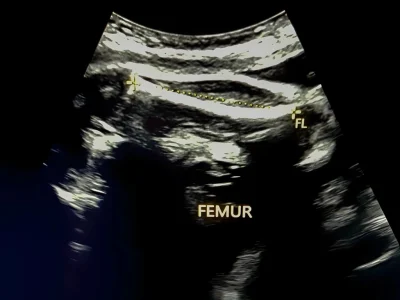

Sự phát triển, cân nặng của bé được phản chiếu đầy đủ trên kết quả siêu âm, hình ảnh thai nhi 31 tuần trong bụng mẹ. Cùng ngắm nhìn những bức hình siêu âm tuyệt đẹp của con tại tuần thai thứ 31 và đừng quên ghi nhớ 1 vài chỉ số quan trọng của […]